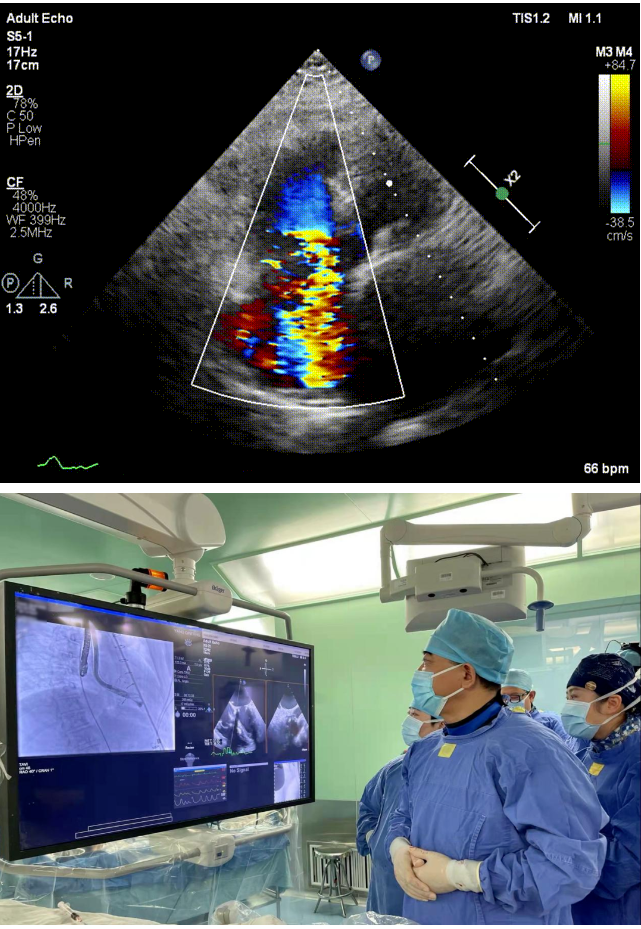

本次接受治療的患者是一名74歲的女性,14年前因風濕性心臟病行二尖瓣生物瓣植入術,合并房顫。近3年來反復因腹脹、納差、下肢水腫入院,藥物治療欠佳。心臟超聲顯示三尖瓣極重度反流(有效反流口面積:0.76cm²,反流容積:79ml),繼發(fā)性右房室增大及上、下腔靜脈增寬(右房上下徑*左右徑:52*41mm,右室左右徑:46mm,下腔靜脈:29mm),右室收縮功能正常,肺動脈收縮壓 43mmHg,左心室射血分數(shù)73% ?;颊呒韧_胸手術史,術前評估STS 評分為7.02分,CRS 9分,無法接受體外循環(huán)下三尖瓣外科手術。面對這一傳統(tǒng)治療無法解決的困境,葛均波院士及其團隊周達新教授、潘文志教授、張源博士、陳莎莎博士及心超室的潘翠珍教授、李偉教授經(jīng)過討論決定,采用創(chuàng)新的Lux-Valve Plus系統(tǒng)為患者進行經(jīng)血管三尖瓣置換。

手術在患者全麻狀態(tài)下進行,采用經(jīng)右側頸靜脈作為入路,將裝載有人工瓣膜的輸送器緩慢推送至右心房;并在經(jīng)食道超聲和DSA的引導下小心調整輸送器角度,將輸送器送入右心室;逐步釋放瓣膜錨定裝置和盤片,調整瓣膜位置后,錨定瓣膜完成植入。術后右房壓明顯下降,從術前的25/10(16) mmHg降至術后即刻的12/7(10) mmHg,術后超聲提示人工三尖瓣同軸性良好,固定牢固,無反流及瓣周漏,手術室即刻拔除氣管插管。